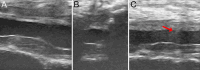

Observations: Here, the authors describe a 57-year-old female with a thoracic intradural arachnoid cyst that recurred despite extensive and initially successful fenestration. Given the failure of fenestration, the authors instead attempted to place a cystoperitoneal shunt. Given how extensive her laminectomy was, the authors elected to perform the procedure under ultrasonic guidance to avoid the large incision required for open shunt placement. The procedure was successful, with gradual improvement in the size of the arachnoid cyst as well as symptomatic improvement.

Lessons: Here, the authors present a unique minimally invasive technique to treat recurrent spinal arachnoid cysts. They successfully demonstrated the feasibility and safety of this approach in shunting the cyst while avoiding the extensive re-exposure often required in such complex cases. https://thejns.org/doi/10.3171/CASE24461.